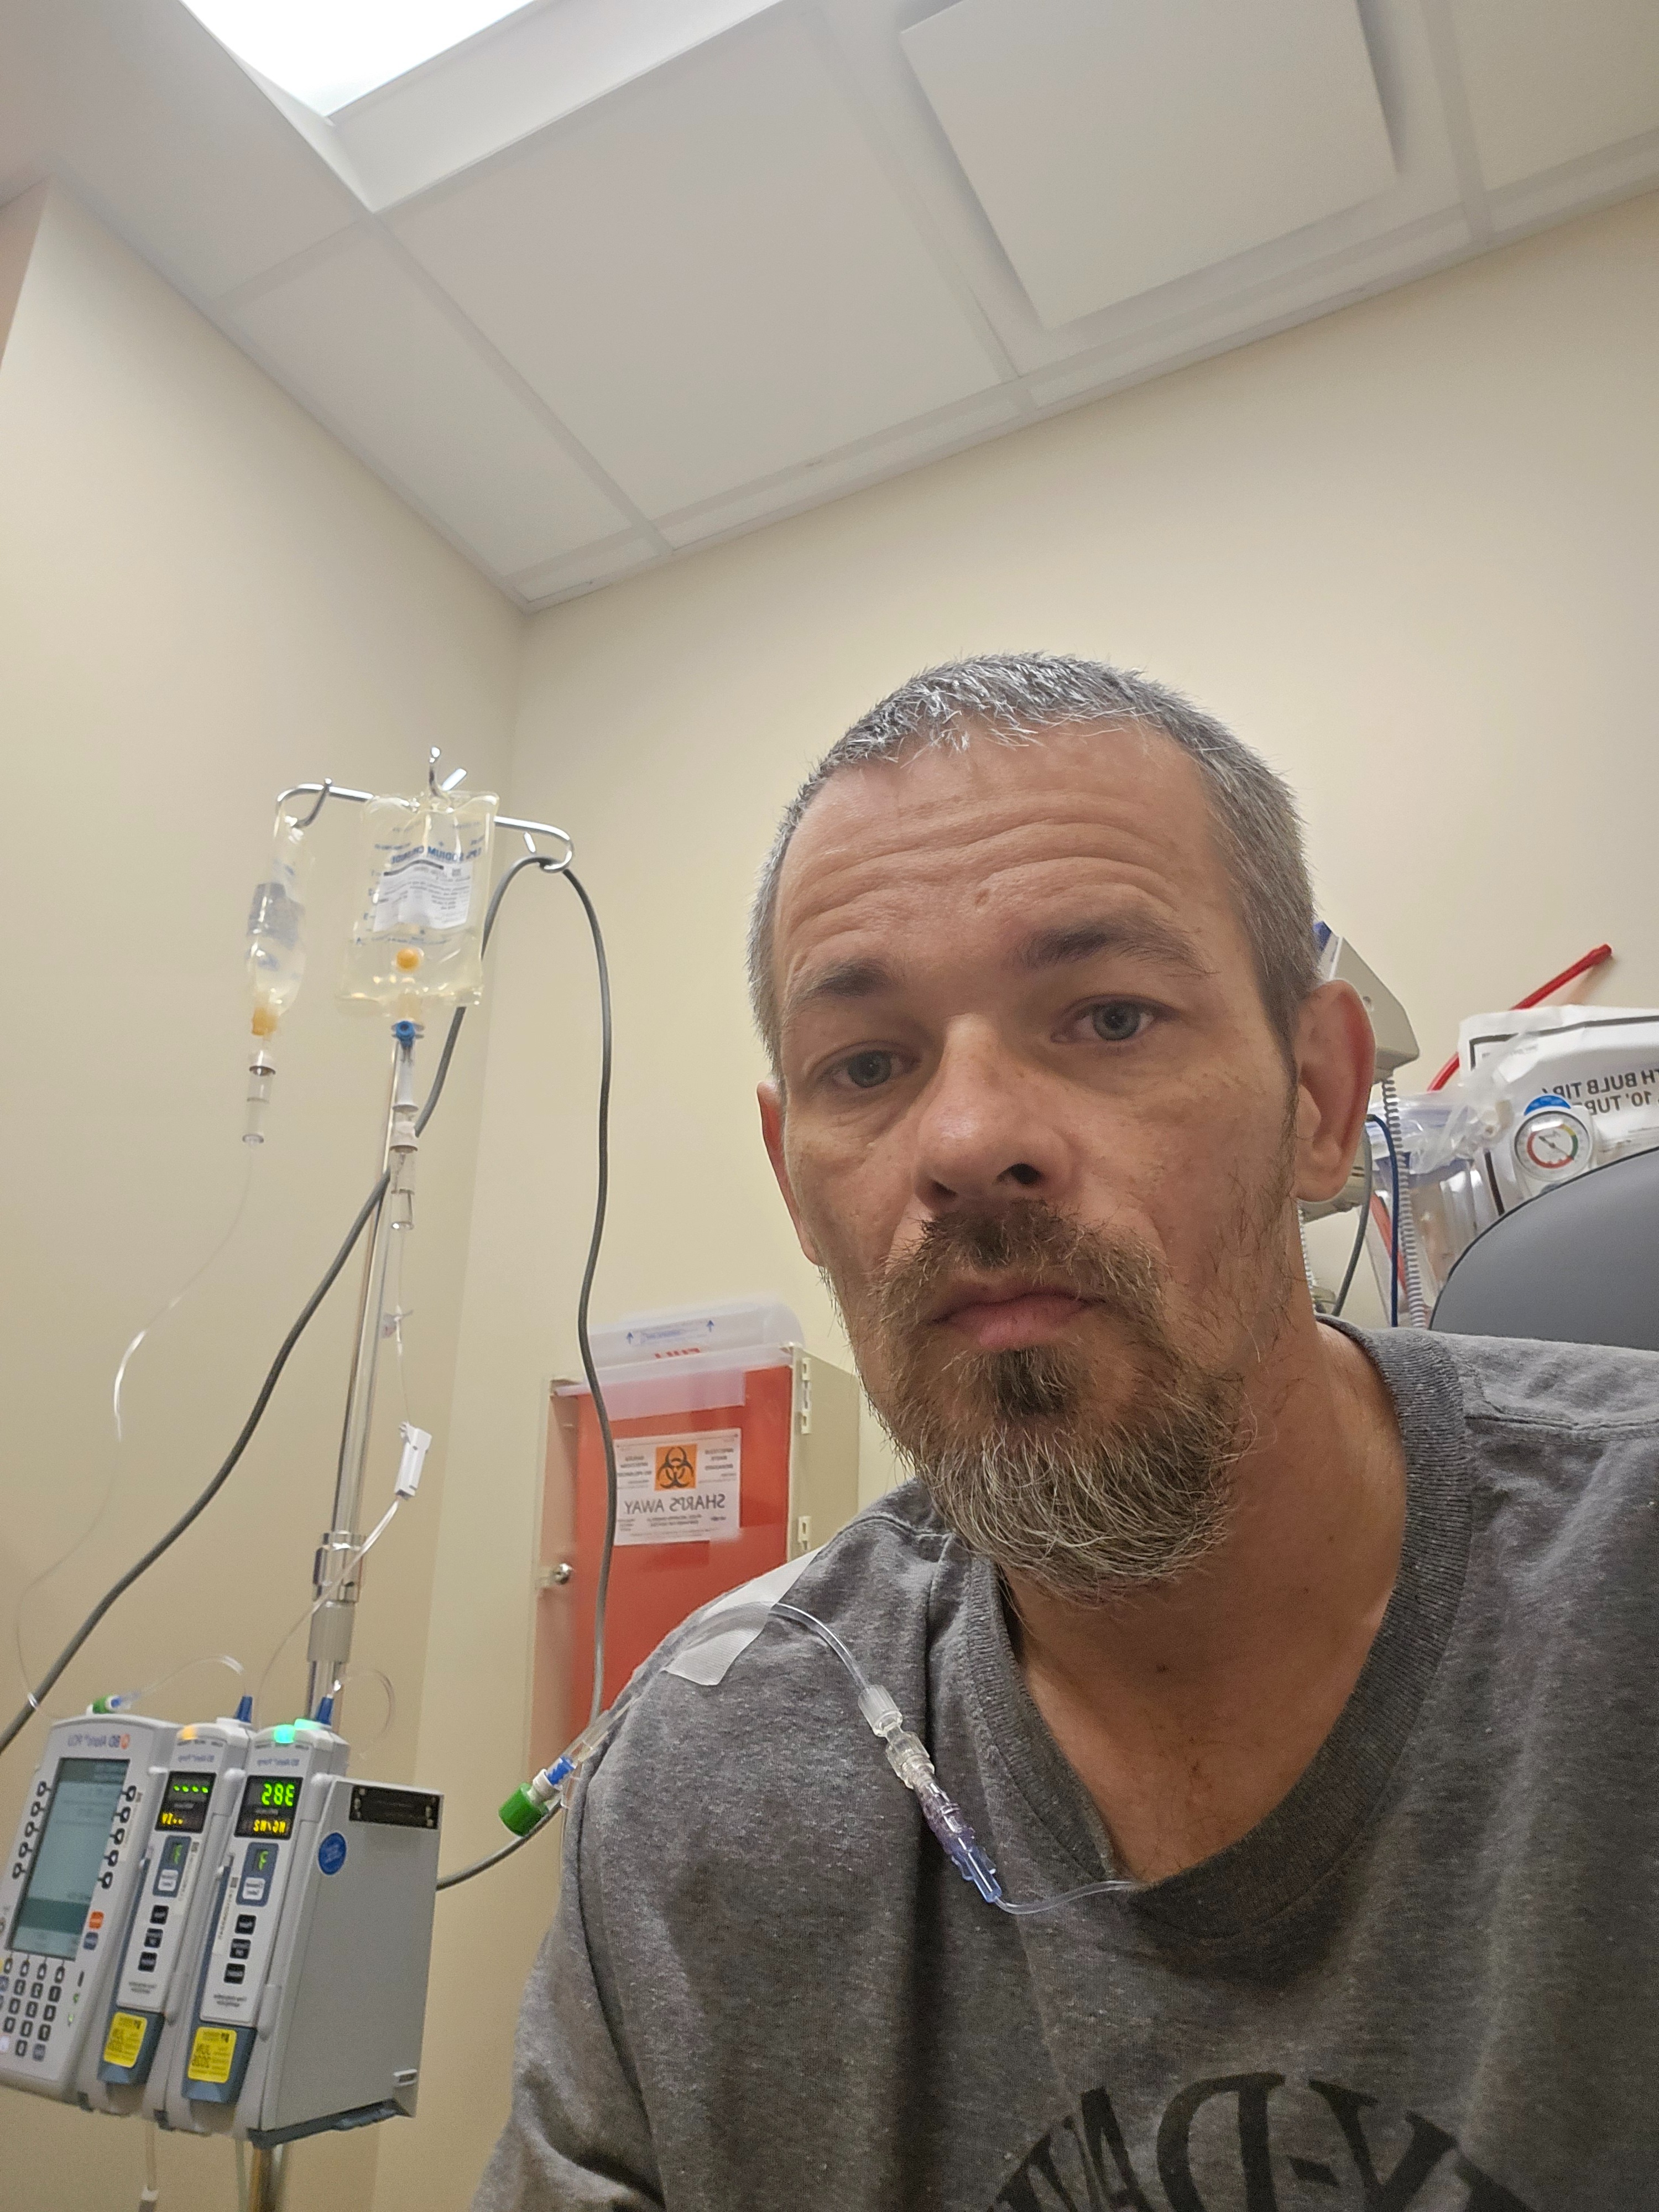

My name is Shane, and on October 30th, I was diagnosed with metastatic poorly differentiated non keratinizing squamous cell carcinoma. Since then, my life has changed dramatically. I am currently undergoing weekly chemotherapy and daily radiation treatments, which has made it impossible for me to work. The physical and emotional toll of treatment is challenging, and the uncertainty about my health and future can feel overwhelming at times.

Because I am unable to work, I am struggling to keep up with my bills and the cost of gas to get to my appointments. Every day is focused on fighting this cancer and making it to my treatments, but the financial stress adds another layer of difficulty. I am reaching out for help so I can cover essential expenses and focus on my recovery without the constant worry about how I will pay for basic needs for me and my kids .